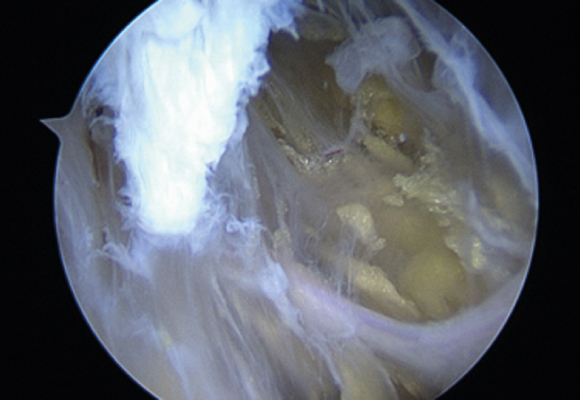

손상된 회전근개를 다듬어 주고 봉합해 주는 수술 시행

ㆍ환자의 동의를 받은 자료이며, 이미지 사진은 실물과 다를 수 있습니다. (16.09.30)